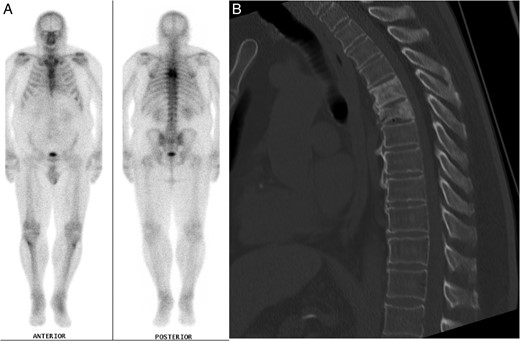

The patient's past medical history included essential hypertension and type 2 diabetes mellitus treated with metformin. Mid-thoracic back pain had also been an active medical problem, which had been under investigation for over 1 year, following a fall. A full blood count had identified lymphopenia and a normocytic, normochromic anaemia. Electrolytes and creatinine, liver function tests, thyroid function tests, vitamin B12, folate, adrenocorticotrophic hormone (ACTH) and cortisol levels were all normal. A computed tomography (CT) scan of his thoracic spine revealed T5 and T6 vertebral crush fractures, with 30–40% loss of height of T6, for which he had been on calcium, vitamin D supplements and zoledronic acid injections. He had not been taking corticosteroid medications and denied previous steroid use. The T5 and T6 thoracic fractures had the appearance of underlying mixed lytic and sclerotic lesions suggestive of neoplasia. A nuclear medicine bone scan highlighted the thoracic lesions but did not identify other sources of abnormal tracer uptake (Fig. 1A and B). A CT scan of the chest, abdomen and pelvis did not detect any other pathology. A T6 vertebral bone biopsy had also been taken a few months prior to this presentation, which only showed reactive bone and cartilaginous fragments with no tumour cells isolated. Tumour markers were negative apart from a β2-microglobulin level of 3.1 mg/l (reference range 0.7–1.8 mg/l).

(A) Nuclear medicine bone scan demonstrating tracer uptake in the T5 and T6 vertebral fractures with no evidence of other abnormal uptake. (B) Mid-sagittal CT scan of the thoracic spine during clinical presentation with ataxia, displaying the vertebral crush fractures and SEL.